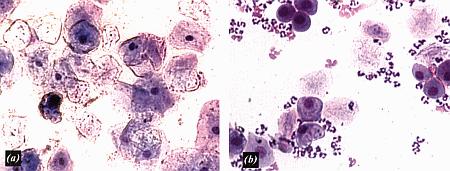

Фиг. 2.2.

Вагинальные выделения кошки (а). Выделения, типичные для фазы эструса. Большая часть клеток представляет собой безъядерные кератинизированные клетки или клетки с пикнотическим ядром. Присутствуют промежуточные клетки (b). Выделения, характерные для метэструса, — «течки», иногда наблюдаемой у кошек в конце эструса. Присутствуют поверхностные и промежуточные клетки, повышено содержание белыми кровяными тельцами. Этот короткий метэструс наблюдается в течение 24–48 часов.